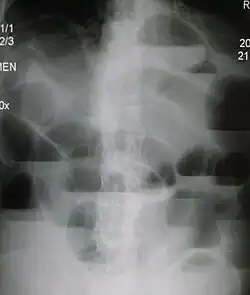

Die Röntgenleeraufnahme des Bauchs im Stehen oder in Linksseitenlage zeigt beim typischen Ileus überblähte Darmschlingen mit Flüssigkeitsspiegeln als Hinweis auf den Ort eines Verschlusses. Je nach Befinden können durch einen Einlauf und/oder eine Passage mit Kontrastmittel Ort und Ursache eingegrenzt werden.